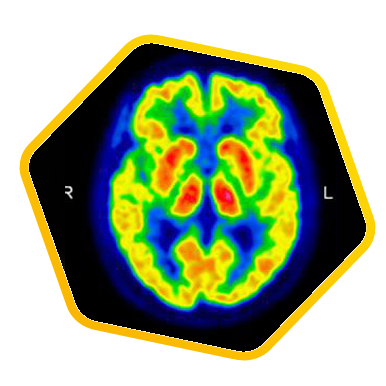

脑神经科

![]() [C-11] PIB |

![]() [C-11] Raclopride |

![]() [F-18] DOPA |